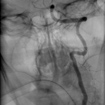

Angioplastía

Carotídea

Se realiza mediante un abordaje de Seldinger convencional (a través de la arteria femoral en la ingle). Cuidadosamente navegamos por las arterias hasta llegar al sitio de la arteria Carótida con estenosis (estrechez). Utilizando unas pequeñas guías metálicas, atravesamos el sitio de la estenosis y posteriormente se utiliza un balón el cual se infla paulatinamente para restablecer el diámetro de la arteria, posteriormente se coloca un Stent autoexpandible (material metálico de forma cilíndrica o tubular que se coloca en la luz de la arteria para mantenerlo permeable. Al terminar la Angioplastía, realizamos controles cerebrales finales para valorar el restablecimiento del flujo sanguíneo cerebral.